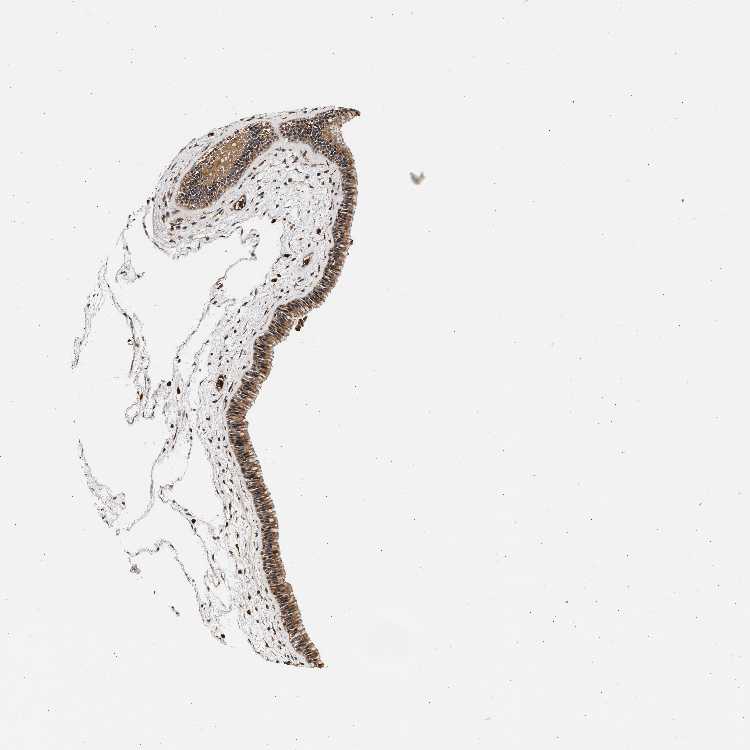

TISSUE PRIMARY DATA NASOPHARYNX Show tissue menu

NASOPHARYNX - Antibody stainingi

Antibody staining in the annotated cell types in the current human tissue is reported as not detected, low, medium, or high, based on conventional immunohistochemistry profiling in selected tissues. This score is based on the combination of the staining intensity and fraction of stained cells.

Each image is clickable and will lead to virtual microscopy that enables deeper exploration of all samples and also displays staining intensity scores, fraction scores and subcellular localization as well as patient and tissue information for each sample.

Antibody HPA012800Antibody CAB020812

Respiratory epithelial cells LowMedium